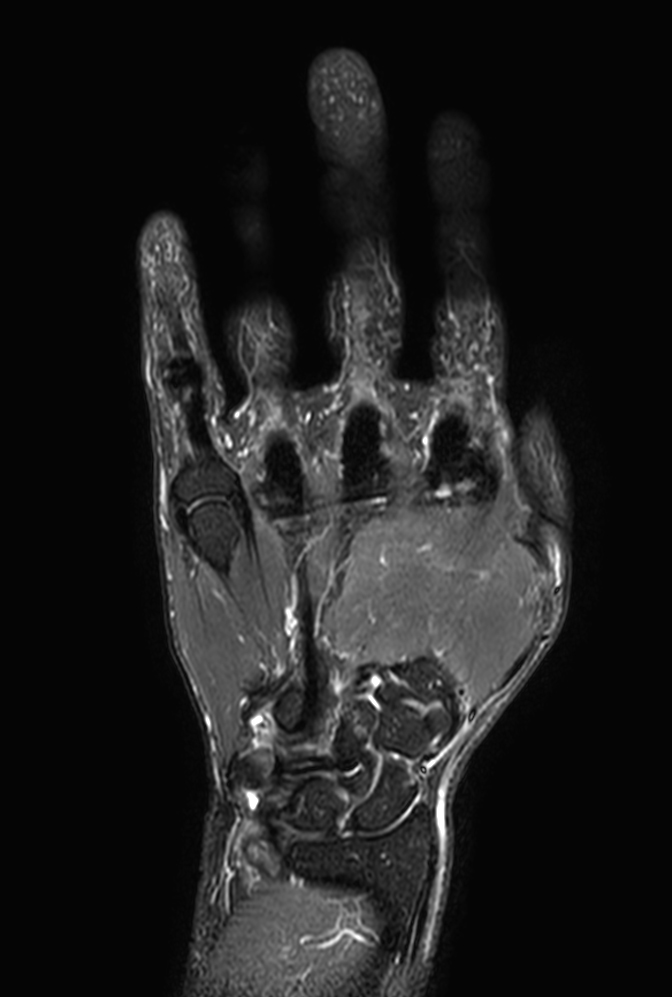

Coronal T1w TSE